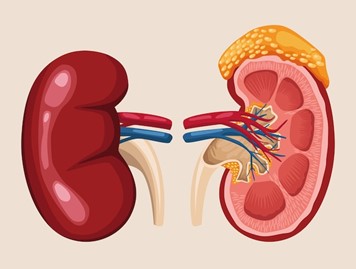

Kidney Transplantation: Know About It

Kidney transplantation is a surgical procedure to place a healthy kidney from a donor into a person whose kidneys no

Renal biopsy is a medical procedure in which a small piece of kidney tissue is removed for microscopic examination. It

Renal biopsy is a crucial medical procedure to diagnose and guide treatment for various kidney conditions. It involves extracting a